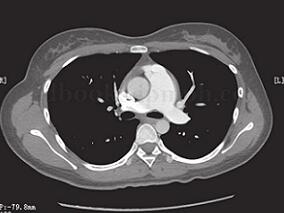

1小时条评论患儿,女,1岁。因生后间断性呼吸困难,怀疑先天性心脏病就诊。经诊断心内结构未见明确异常,而是由一种罕见的先天性肺血管畸形所造成。详见以下病例 【临床资料】 患者,女,1岁。因生后间断性呼吸困难,怀疑先天性心脏病(简称先心病)就诊。查体:无特殊。胸片...